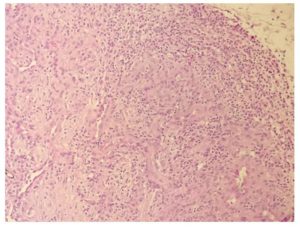

Figura 3.- Proliferación lobular de estructuras vasculares de pequeño diámetro.

Figura 4.- Estructuras vasculares asociadas a células ovoides fusiformes de núcleos agrandados con cromatina

vesicular abierta.

Figura 5.- Ligero infiltrado inflamatorio linfocitario perilesional y vasos linfáticos dilatados.

El diagnóstico se realiza sobre todo mediante el estudio histopatológico, que es el gold estándar, para confirmar el angioma en penacho y para excluir otras malformaciones vasculares y tumores, siendo característica la presencia de células capilares

y endoteliales distribuidas en forma de “bolas de cañón”. En la infancia, el angioma en penacho se debe diferenciar del nevo en forma de fresa y del hemangioendotelioma de Kaposi y, en los adultos, el angioma en penacho debe diferenciarse del sarcoma de Kaposi y del angiosarcoma de bajo grado 5.